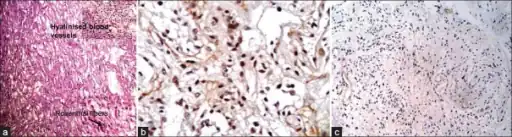

-

a-c) Photomicrograph shows microcystic areas in pilocytic astrocytoma -

Histopathology of pilocytic astrocytoma (grade I WHO). -

Histopathology of Rosenthal-fibres. H&E staining showing these elongated eosinophilic structures in the case of pilocytic astrocytoma.

Under the microscope, the tumor is seen to be composed of bipolar cells with long "hair-like" GFAP-positive processes, giving the designation "pilocytic" (that is, made up of cells that look like fibers when viewed under a microscope[6]). Some pilocytic astrocytomas may be more fibrillary and dense in composition. The presence of Rosenthal fibers,[7] eosinophilic granular bodies, and microcysts can often be seen. Myxoid foci and oligodendroglioma-like cells may also be present, though these are not specific to pilocytic astrocytoma. Long-standing lesions may show hemosiderin-laden macrophages and calcifications.